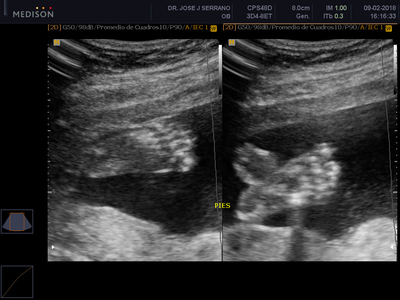

Esta ecografía busca detectar anomalías fetales explorando detalladamente cabeza, cara, tórax, abdomen, genitales y extremidades, así como todos los órganos del bebe (cerebro, corazón, pulmones, riñones, etc). También se tomarán las medidas fetales para compararlas con el tiempo de embarazo y descartar problemas de desarrollo y crecimiento. Además, se evaluarán los movimientos del feto, su patrón de respiración, tono fetal, flujo sanguíneo, entre otros.